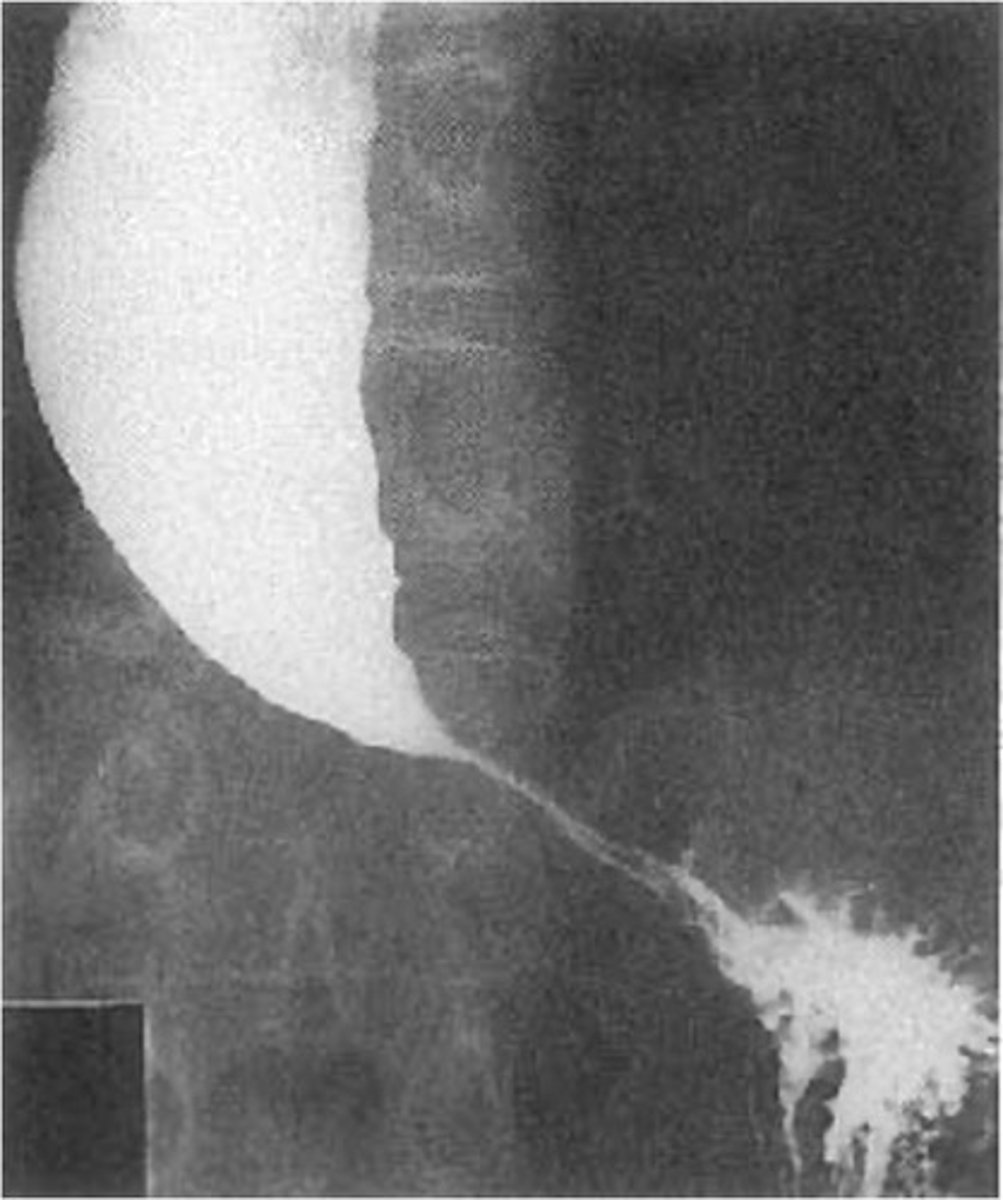

Achalasia

Achalasia (pic 5)

Achalasia (pic 2)

Achalasia (pic 3)

Achalasia (pic4 )